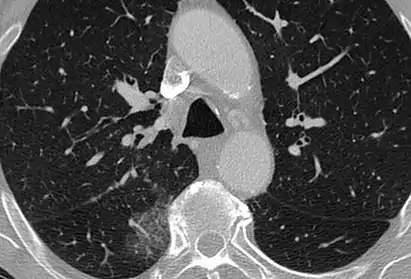

CT image showing centrilobular pattern of GGOs in patient with pulmonary tuberculosis. Note the small, nodular areas of increased attenuation in both lungs.

Centrilobular

Centrilobular GGOs refer to opacities occurring within one or multiple secondary lobules of the lung, which consist of a respiratory bronchiole, small pulmonary artery, and the surrounding tissue.[3] A defining feature of these GGOs is the lack of involvement of the interlobular septum. Potential causes of centrilobular GGOs include pulmonary calcifications from metastatic disease, some types of idiopathic interstitial pneumonias, hypersensitivity pneumonitis, aspiration pneumonitis, cholesterol granulomas, and pulmonary capillary hemangiomastosis.[6]